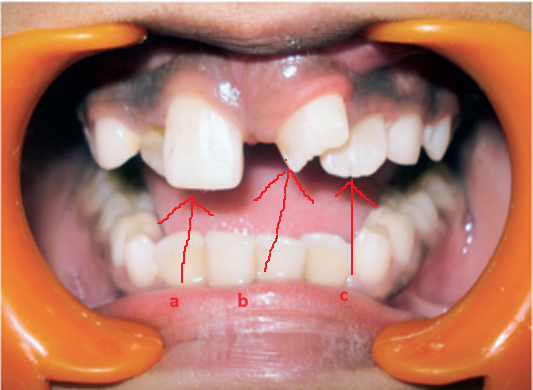

Sự hiện diện của răng thừa sẽ gây cản trở quá trình mọc và sắp xếp của các răng cửa hàm trên. Chúng có thể làm lệch hoặc ngăn cản sự mọc của các răng cửa giữa; gây mọc lệch vị trí, dịch chuyển hoặc xoay răng cửa hoặc răng cửa bị lệch về phía môi. Các biến chứng ít gặp hơn liên quan đến răng cửa vĩnh viễn bao gồm giãn chân răng đang phát triển, tiêu chân răng và chết tủy răng. Ngoài ra, các biến chứng liên quan đến răng thừa bao gồm mọc răng thừa vào khoang mũi, xoang hàm và phát triển nang răng đã được báo cáo.

Răng thừa làm cho R21 mọc thưa và lệch về phía môi Răng thừa (a) làm R11 (b) bị kẹt không mọc ra được

Răng thừa gây nang xương hàm trên Răng thừa mọc vào tiền đình mũi

Hình 2: Một số biến chứng của răng thừa